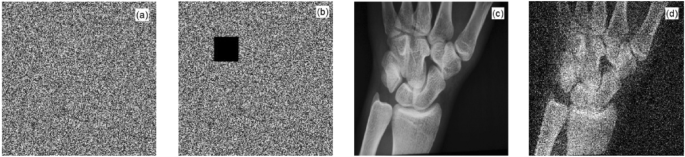

Analysis of an anti-shear attack

To test the anti-cropping ability of the algorithm, we cut out a 40 × 40 sized image from the middle of MRI's encrypted image, as shown in Fig. 11b, and then decrypted the cropped ciphertext image. The decrypted image is shown in Fig. 11d. Figure 11a shows the original encrypted image and Fig. 11c shows the decrypted image of the original encrypted image. Comparing Fig. 11c and d, we observed that the pixel values of some points in Fig. 11d had changed; however, the approximate information of the plaintext image was still displayed. Therefore, the encrypted images still had a certain decryption effect after being subjected to cropping attacks.